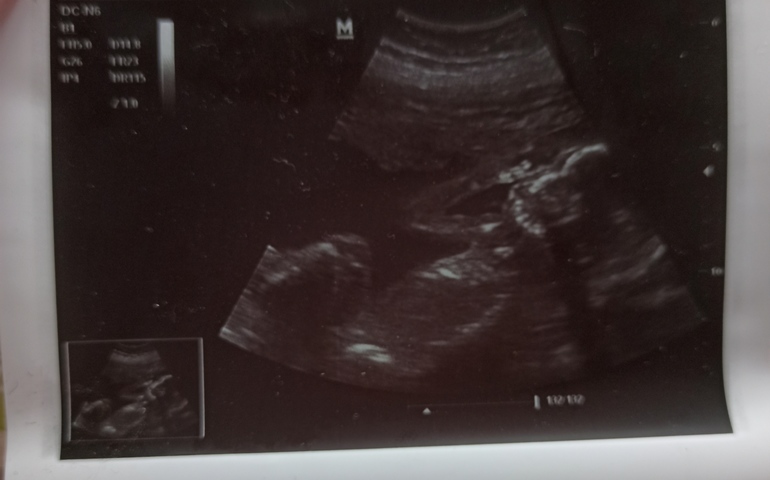

Что такое на фотке узи? Узи в 18,2 недели и пол малыша

Пол под ?

Думаю девочка

А кто у нас? Подскажите пожалуста)

Девочка🌸

А у меня можете глянуть? Понимаю, что глупый вопрос, но не такой перчик нам показывали с двумя предыдущими мальчиками. Там был и перчик и мошонка, а где здесь она, да и перчиик полосатый и острый? Или я тороплю события? 😂 Накручиваю себя, уж очень хотелось девочку. Но и мальчику будем рады🤗.